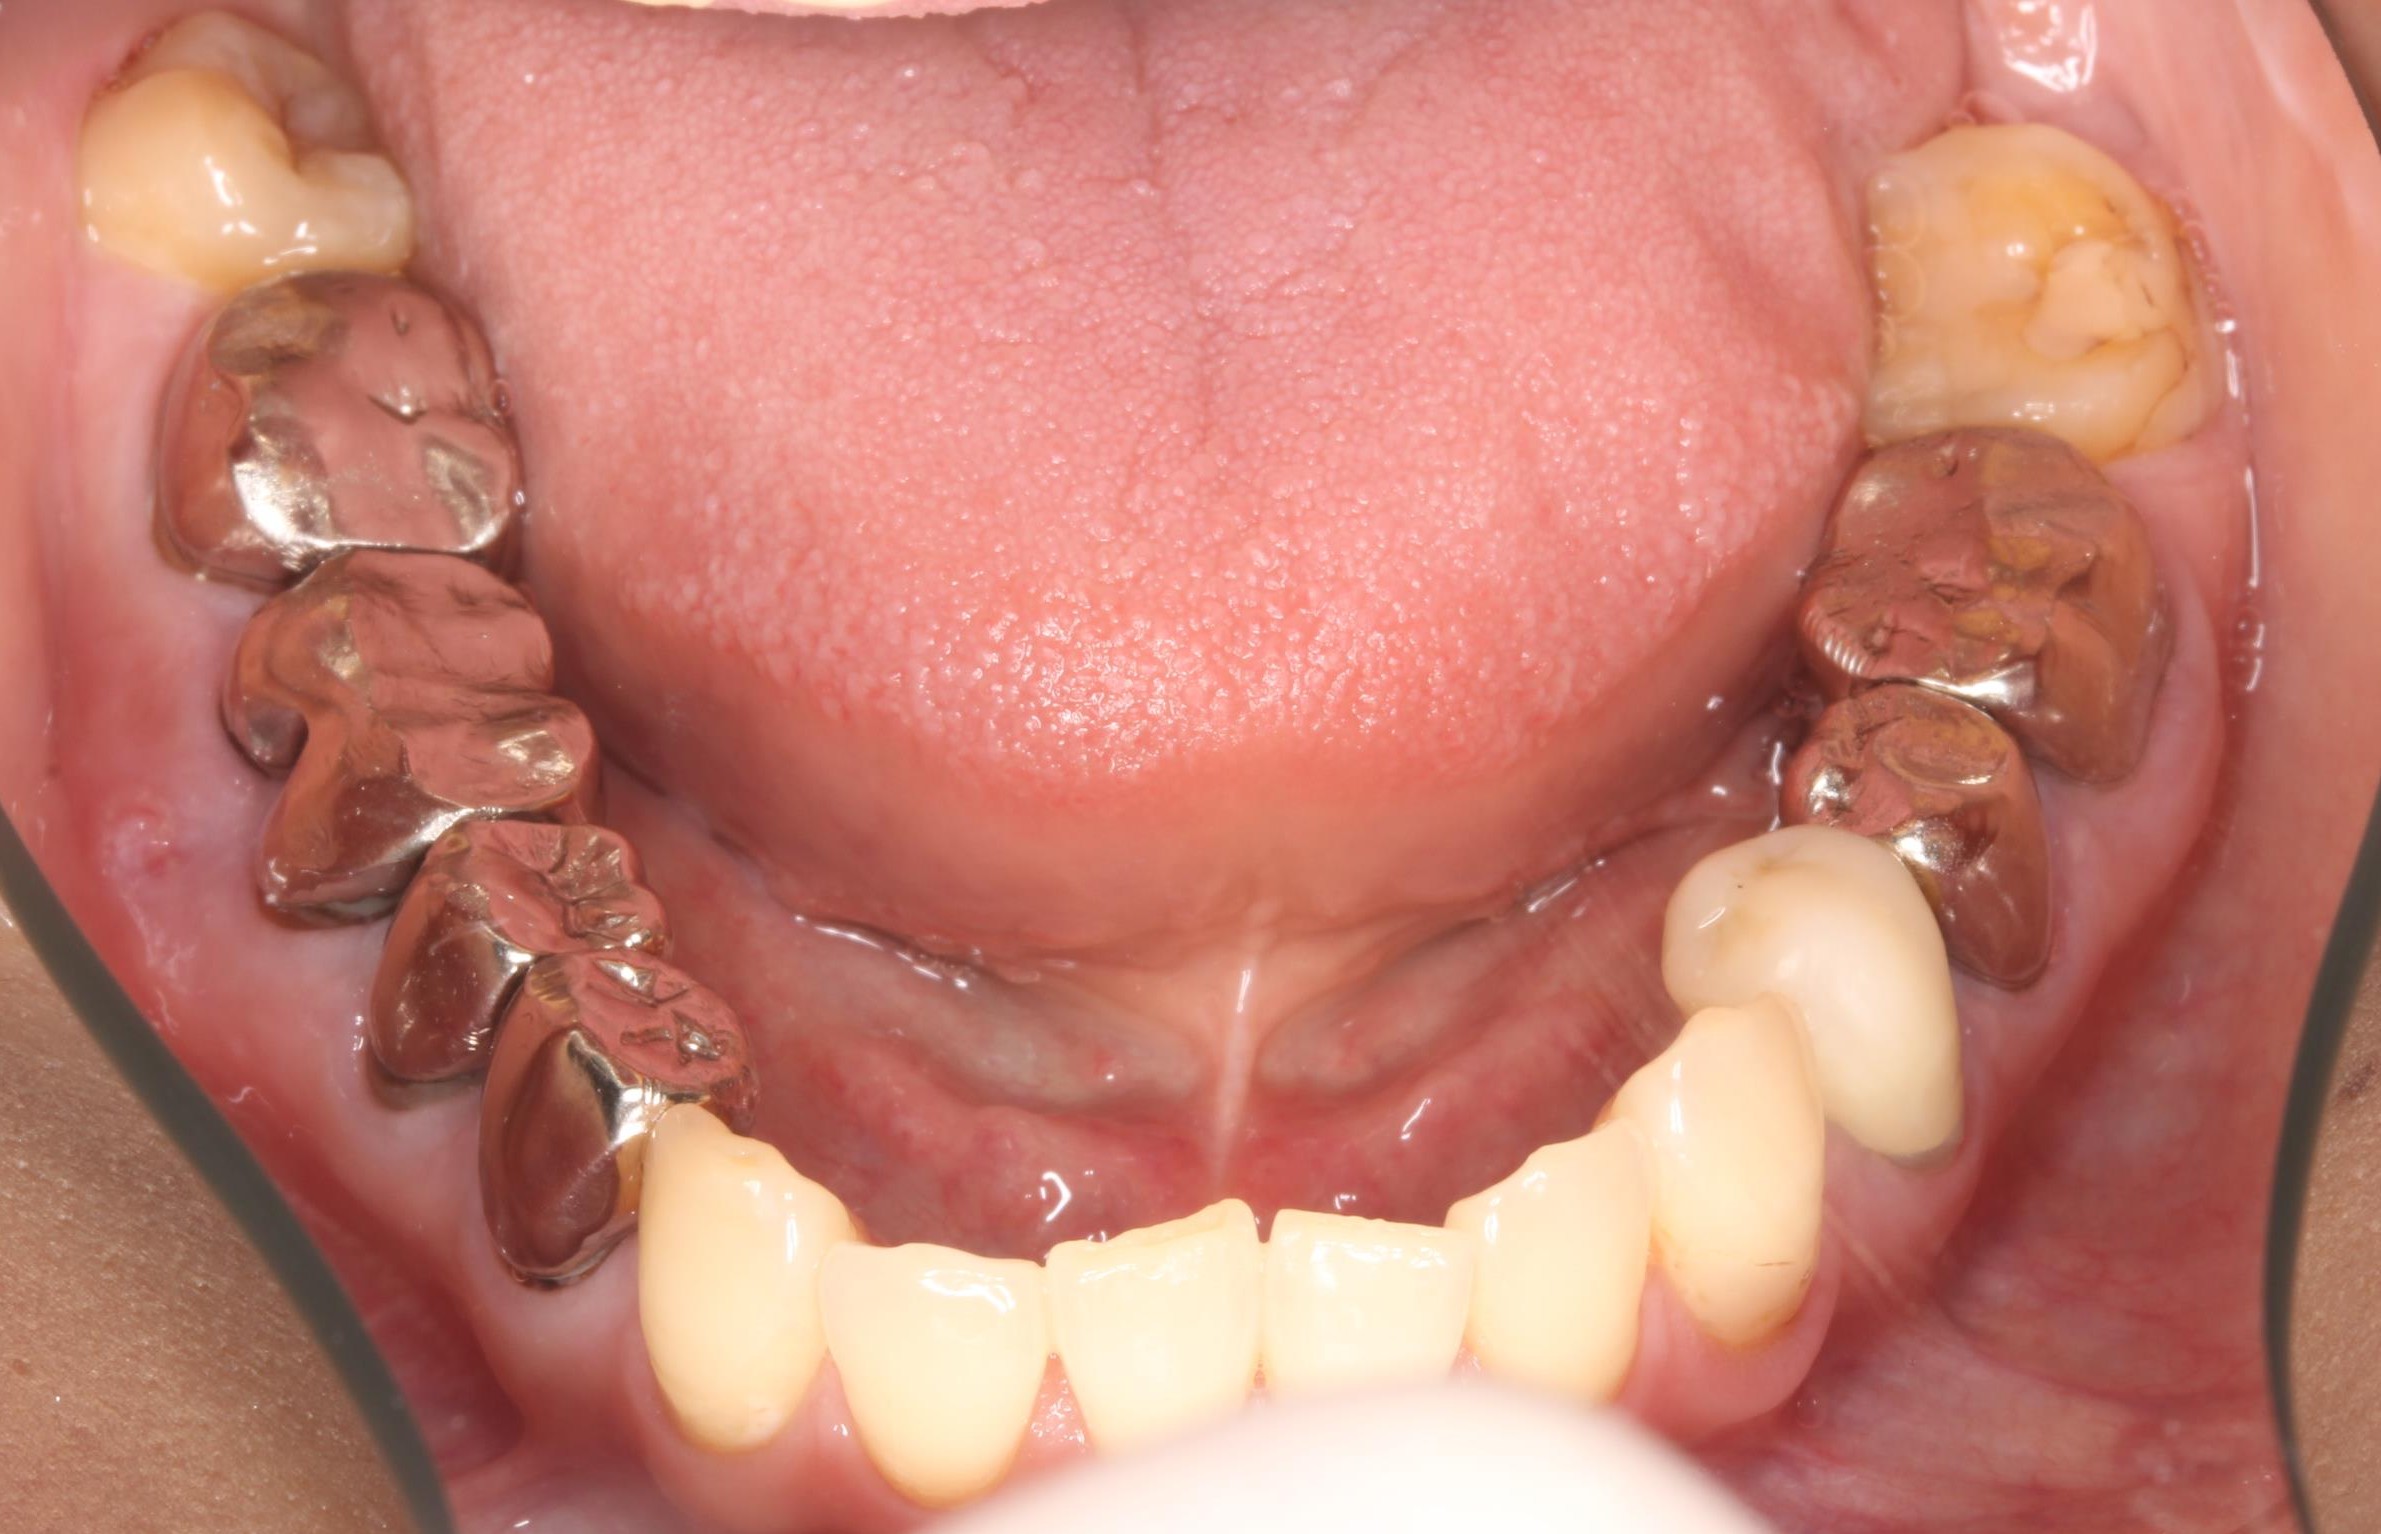

症例02

70代 男性 咬み合わせが強く多くの歯がすぐに壊れる

| 主訴 | 咬み合わせが強く、治療をしてもつくった歯がすぐに壊れる。 他院ではインプラントをいれることも難しいため、断られた。 |

|---|---|

| 年代・性別 | 70代 男性 |

| 治療部位 | 下顎両側 5,6 上顎右側 4 6のインプラントブリッジ ※全顎的に、臨床的歯冠長延長術(クラウンレングスニング)を行い、セラミッククラウンの強度を増しています。 |

| 治療費用 | インプラント 440,000円×6本 |

| 手術回数 | 下顎1回 上顎1回 |

| 治療期間 | 下顎6ヶ月 上顎6ヶ月 |

| 手術時間 | 下顎90分 上顎60分 |

| 治療回数 | 下顎1回 上顎1回 |